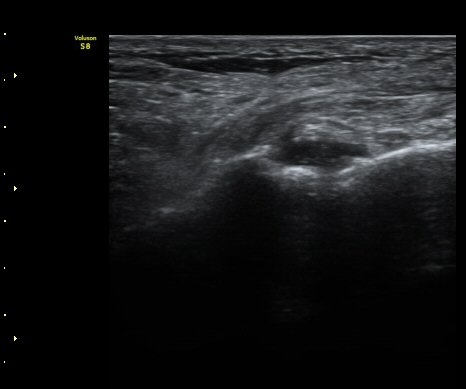

ÃÊÀ½ÆÄ °Ë»ç

Á¾°ñÀÔ¹æ°ñÀδëÀÇ Á¾´Ü¸é°Ë»ç¿¡¼­ ÀδëÀÇ Á¾°ñ ºÎÂøºÎ ÆÄ¿­ÀÌ °üÂûµÊ(»çÁø 1, 2, 3).

Àδë Á¾°ñºÎÂøºÎ Á¾´Ü¸é°Ë»ç¿Í Ⱦ´Ü¸é°Ë»ç¿¡¼­ Á¾°ñÀÇ °ß¿­°ñÀýÀÌ °üÂ÷µÊ(»çÁø 4, 5).

Á¾°ñÀÔ¹æ°ñÀÎ´ë ¿ÜÃø Á¾´Ü¸é°Ë»ç¿¡¼­ ¼ö¾×Àú·ù°¡ °üÂûµÊ(»çÁø 6, 7).

ÃÊÀ½ÆÄÀ¯µµÇÏ Á¾°ñÀÔ¹æ°ñ°ñ°üÀý ºÎÇϰ˻翡¼­ °í³ªÀýÀÇ ºÒ¾ÈÁ¤ÀÌ °üÂûµÊ(÷ºÎÆÄÀÏ)